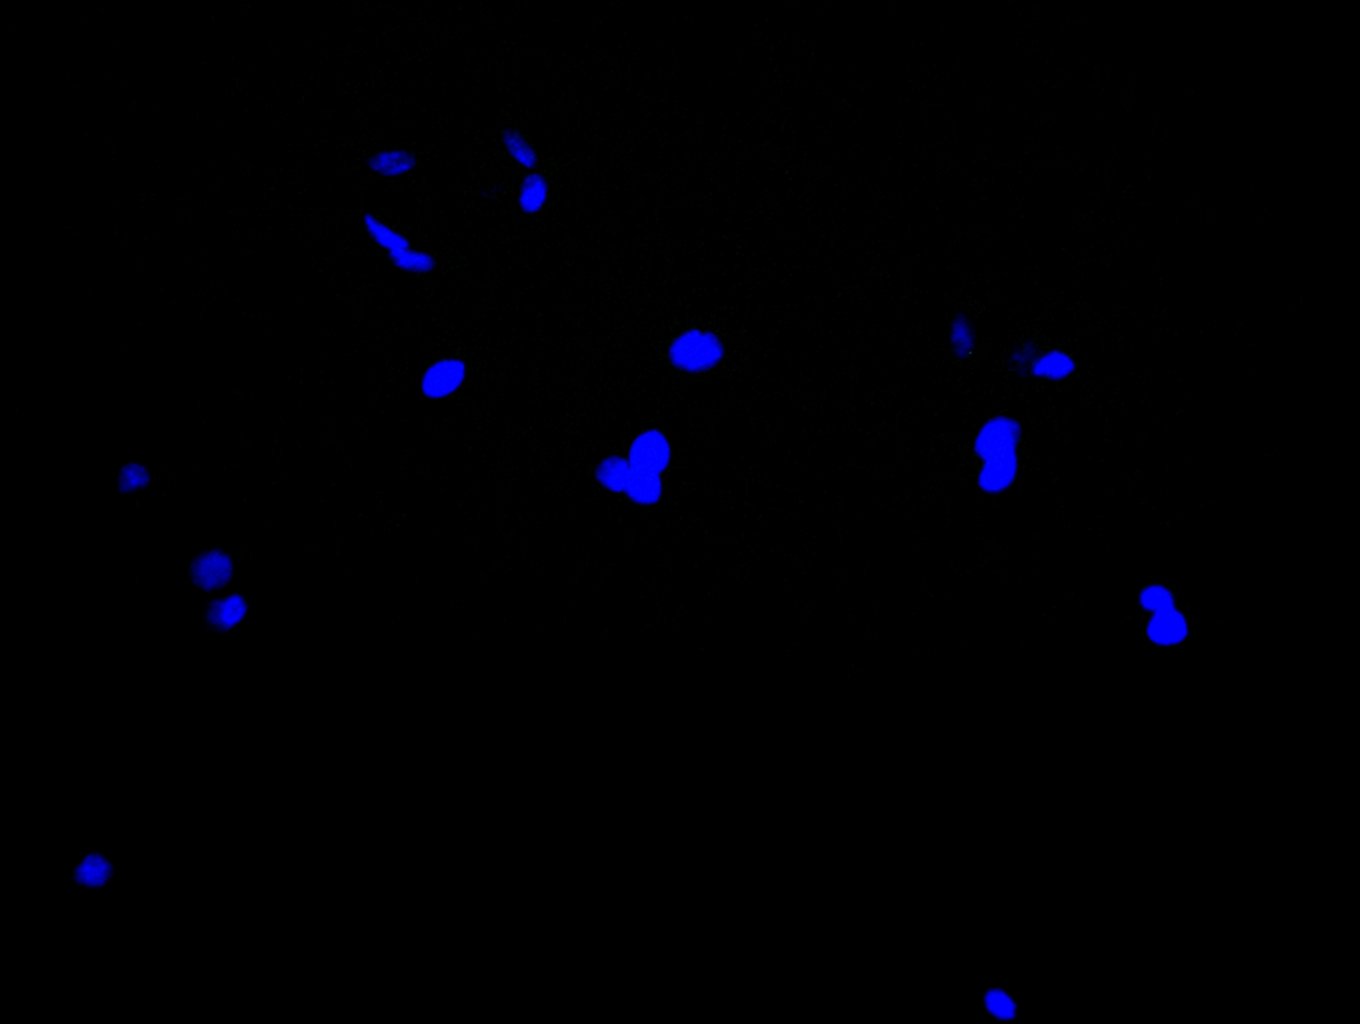

Immunofluorescence staining of Hela cell with 5% goat serum, counter-stained with DAPI. The cells were fixed in 4% formaldehyde and blocked in 10% normal Goat Serum. The cells were then incubated with the antibody overnight at 4C. The secondary antibody was Alexa Fluor 488-congugated AffiniPure Goat Anti-Rabbit IgG(H+L).

Immunofluorescence staining of HepG2 cell with 5% goat serum, counter-stained with DAPI. The cells were fixed in 4% formaldehyde and blocked in 10% normal Goat Serum. The cells were then incubated with the antibody overnight at 4C. The secondary antibody was Alexa Fluor 488-congugated AffiniPure Goat Anti-Rabbit IgG(H+L).